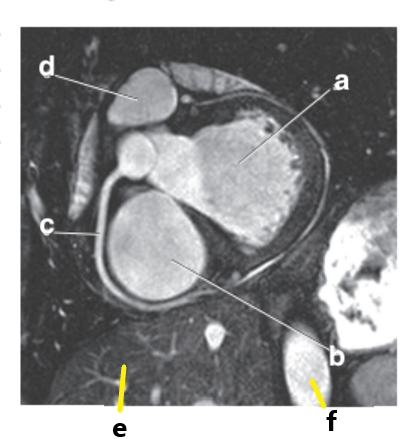

Which letter is the Pulmonary trunk ?

d

Which letter is the Descending aorta ?

f

Which letter is the superior vena cava ?

Left atrium

What is letter b ?

Left ventricle

What is letter c ?

What is letter d ?

Pulmonary trunk